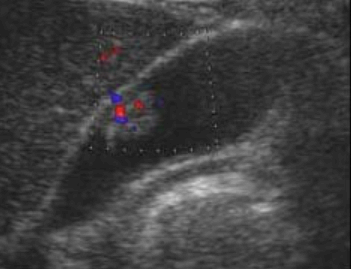

- Color doppler 적용 시 twinkle artifact 가 보인다

- 1cm 미만의 고에코의 종괴 (hyperechoic mass) : 담석에 비해 에코가 낮고, 담낭벽보다는 고에코로 보임

- 담낭벽에 붙어 체위변화 시 이동이 없다

- 후방음영이 없다